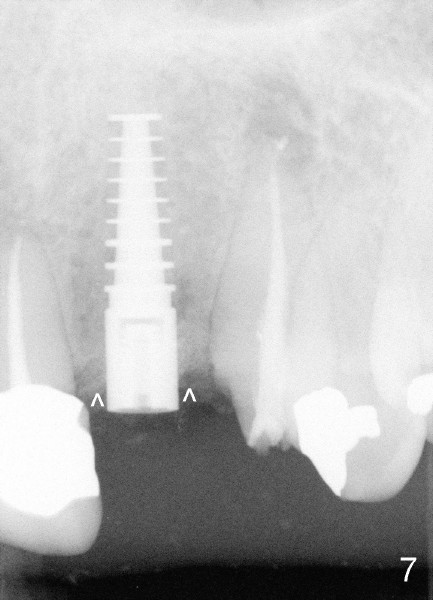

Segmental Osteotomy for Misplaced Implant

This corrective surgery was performed by Dr. Bernee Dunson.

Xin Wei, DDS, PhD, MS 1st edition 12/21/2011, last revision 12/23/2011